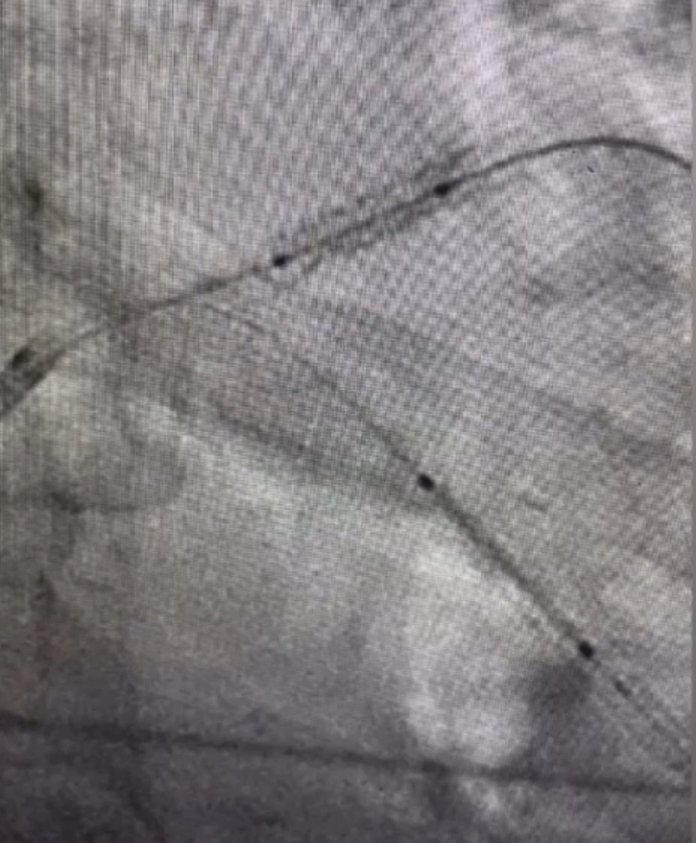

Yurtdışında stenti ana damara kaçırılan hasta bnm yakınım bu operasyonu İstanbul'da başarı ile gerçekleştiren Prof.dr.Nihat Özer Demekki neymiş Türk hekimlerinin değerini bilmek gerekirmiş.

Yurtdışında stenti ana damara kaçırılan hasta bnm yakınım bu operasyonu İstanbul'da başarı ile gerçekleştiren Prof.dr.Nihat Özer

Demekki neymiş Türk hekimlerinin değerini bilmek gerekirmiş.